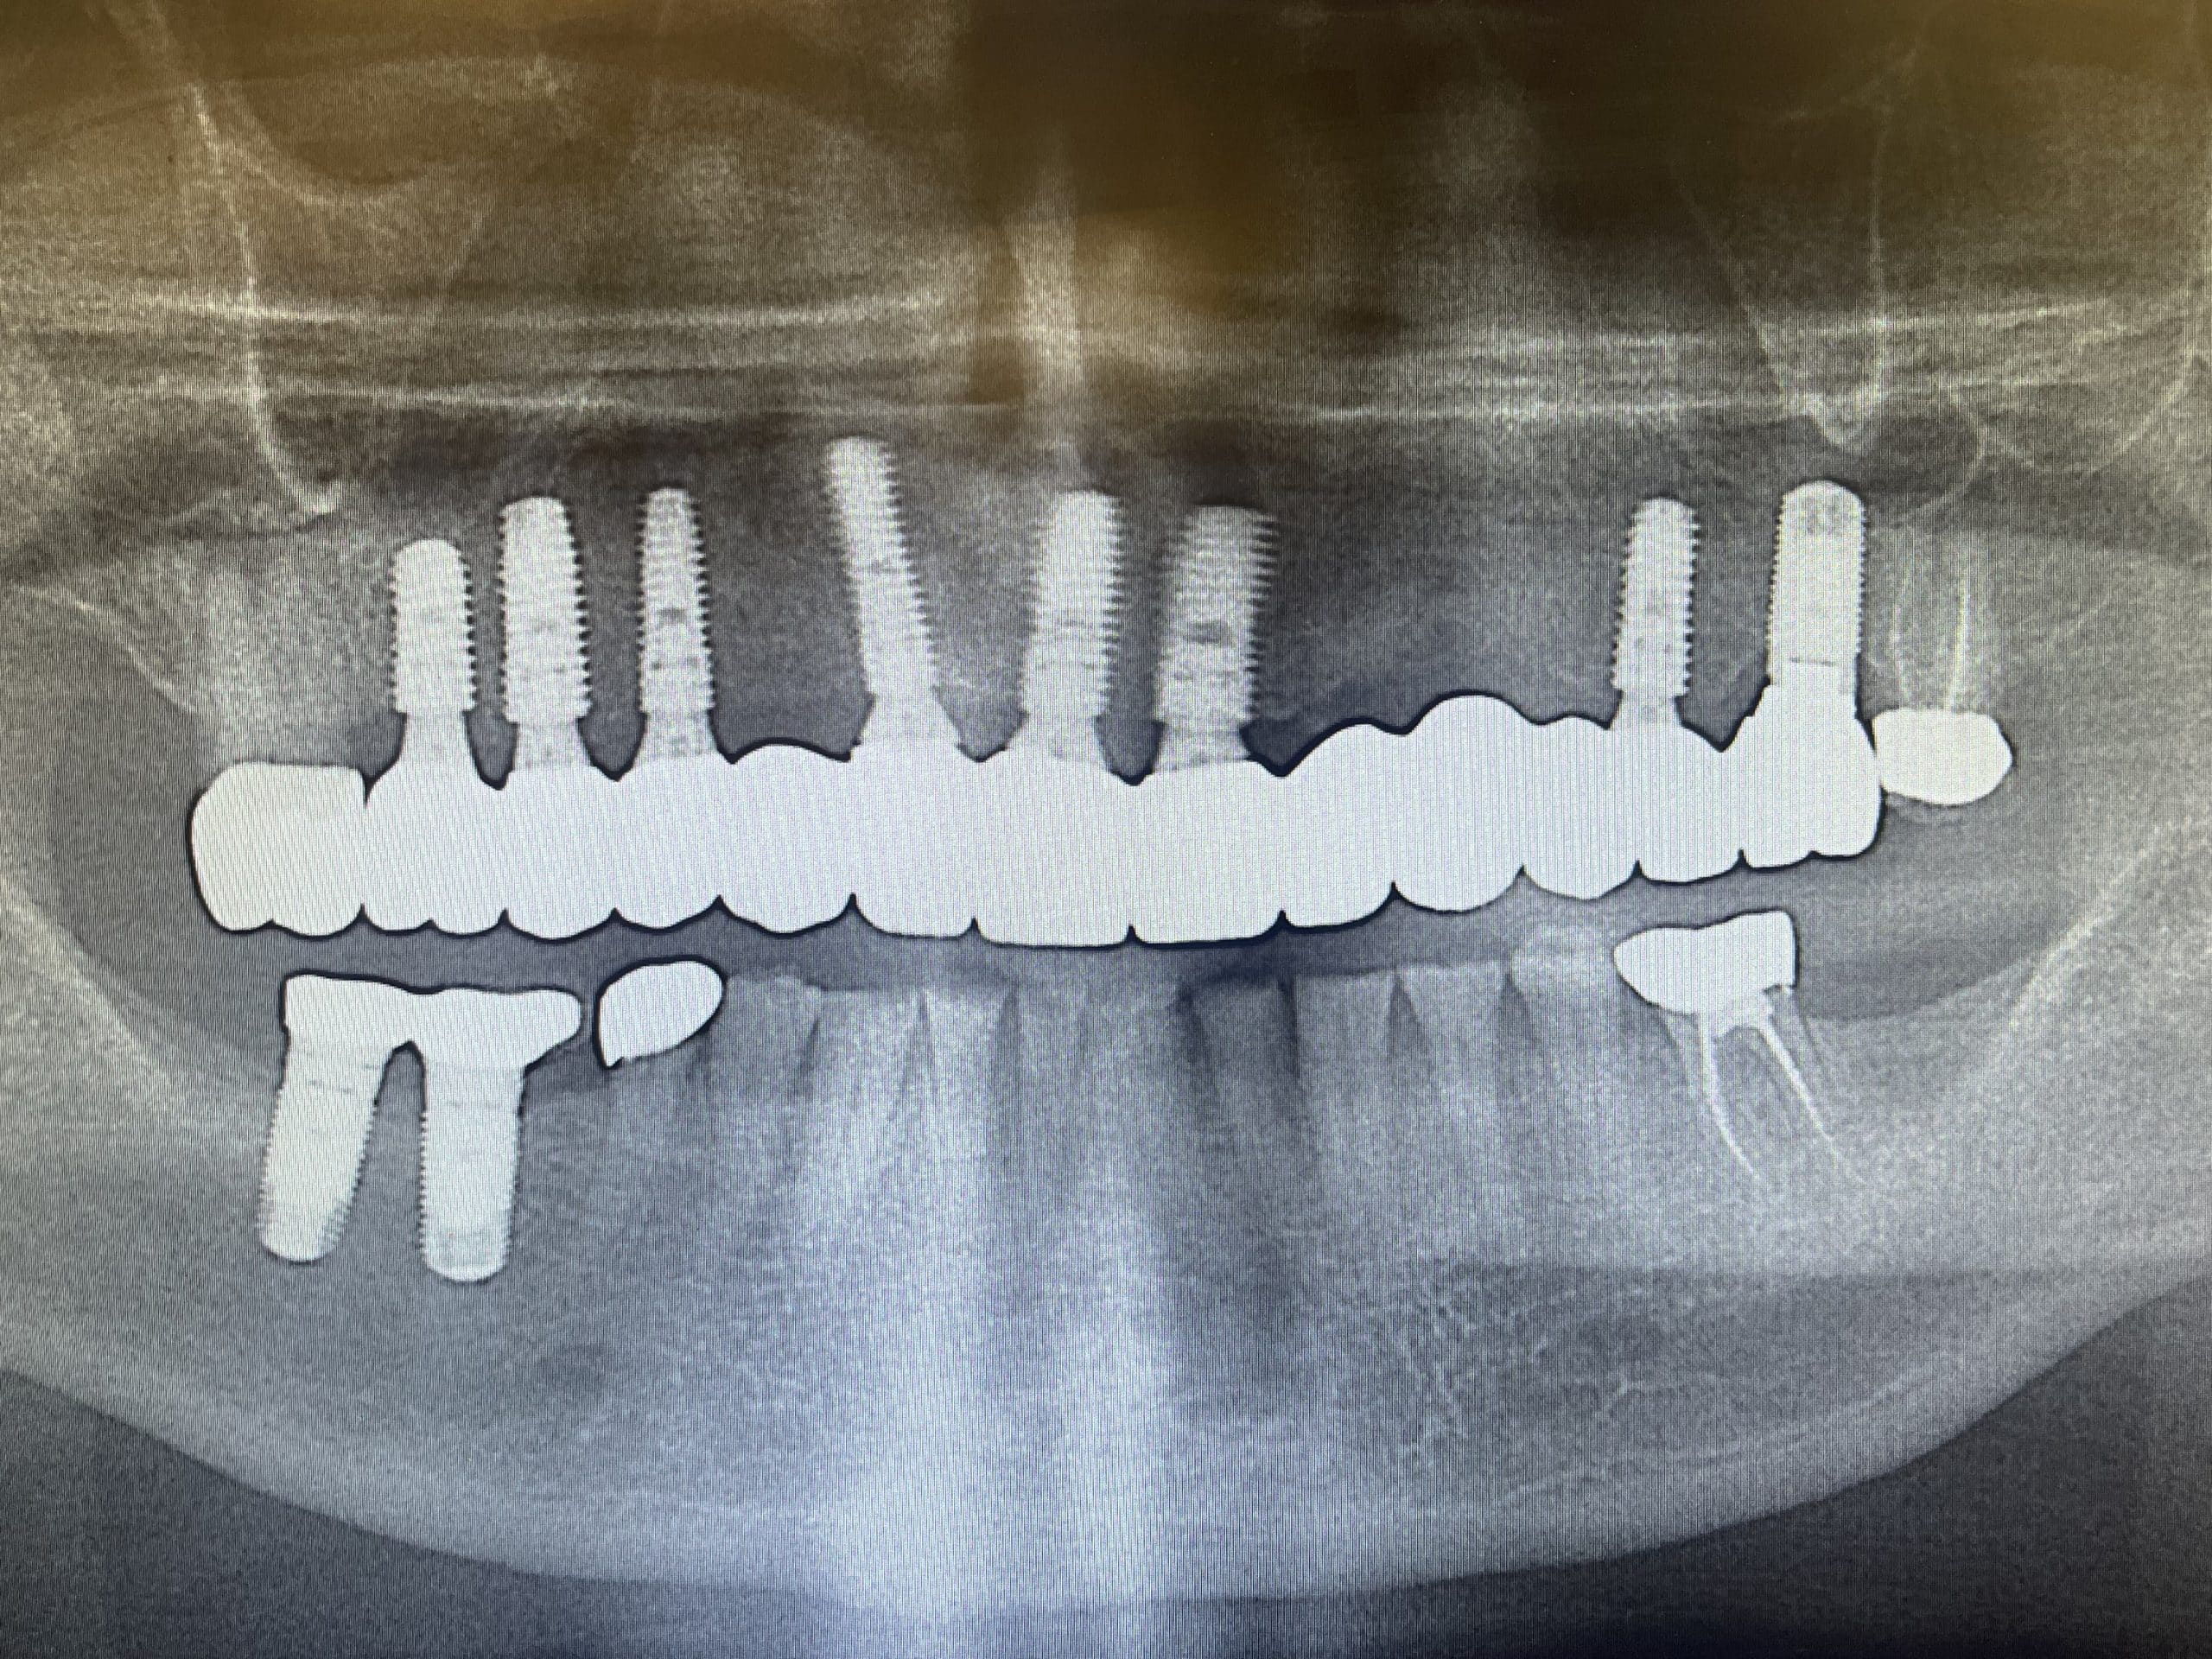

We will perform a thorough oral evaluation and use the most advanced dental technology to fully diagnose and customize your new smile design. Digital imaging (known as a CT scan) captures accurate intraoral data of your entire mouth. From there, detailed plans are designed, created and revised. Once finalized, the prosthetic design and surgical guide are fabricated.

On the day of your implant placement, your personalized surgical guide is used to accurately position the implant with sub-millimeter accuracy. The surgical procedure is amazingly quick and painless. A healing cover is then placed on top of the implant which allows the implant and tissue to heal.